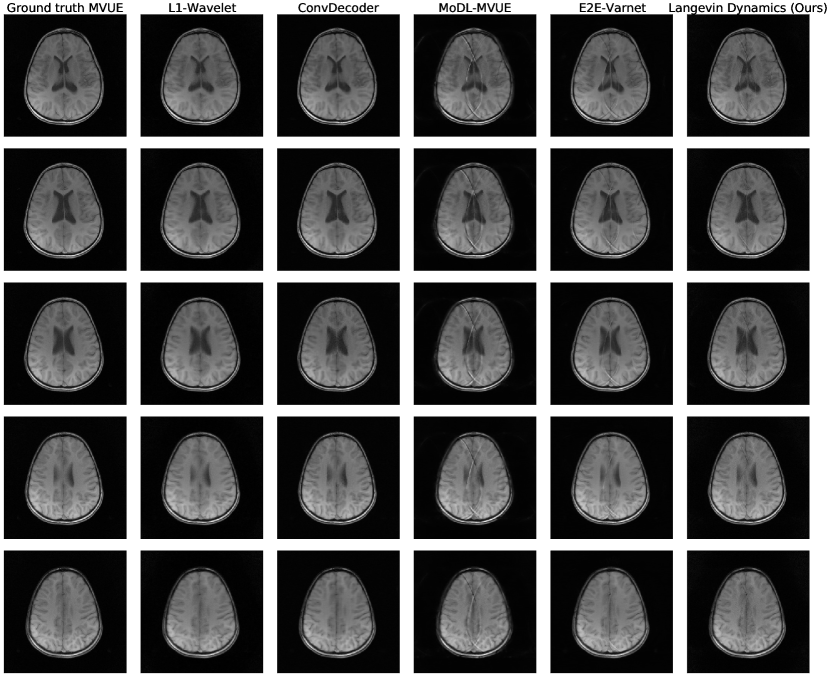

Refer to caption

Figure 1: Comparison of reconstruction methods for in-distribution, sampling-shift, and anatomy-shift images. All methods and hyperparameters were optimized on T2-weighted brain scans with a vertical sampling mask, and tested at higher accelerations, horizontal masks, and on knee & abdomen scans. Our reconstructions are competitive with state-of-the-art methods, and introduce fewer artifacts out of distribution. All measurements are multicoil k-space from the NYU fastMRI dataset and the supervised baselines are trained from scratch on MVUE targets for a fair comparison.

Our main results are succinctly summarized in Figure 1: we achieve equivalent reconstruction performance using a reduced training set when evaluated in-distribution and are robust when evaluated out-of-distribution.

Figure 1 (top three rows) shows qualitative results and Figures 2a & 5a respectively show PSNR & SSIM values, for the case where there is no mismatch between the training and inference sampling patterns. As the baselines were trained to maximize SSIM at R=3& 6𝑅36R=3\;\&\;6, we see that they achieve better SSIM scores than us at these accelerations, although there is clear aliasing in the baselines at R=6𝑅6R=6. We achieve better PSNR values at these accelerations, which supports the claim that our method does not overfit to a particular metric (Theorem 3.4). This also highlights the importance of qualitative evaluations in medical image reconstruction and the limitations of existing image quality metrics [65]. From the third row of Figure 1, and Figures 2a & 5a, we notice that our method surpasses baselines at higher accelerations.

Figure 1 (fourth row) shows qualitative reconstructions when the measurements are obtained from an equispaced, horizontal sampling mask, with an acceleration factor R=3𝑅3R=3. It can be observed that the reconstructions output by E2E-VarNet show aliasing artifacts. Based on the statistical results in Figure 2b & 5b, our method retains its performance.

Finally, Figures 2d & 5d show PSNR and SSIM scores obtained on fastMRI knee reconstructions, while Figure 1 (bottom row) shows the accompanying qualitative plots. This anatomy is challenging especially because of the poor signal-to-noise ratio conditions, which can be seen even in the ground-truth image. It can be noticed that this is the most severe shift for all methods, but our approach still shows the best performance at R=2,4𝑅24R={2,4} and a significantly lower variance. Appendix D shows more examples of knee reconstructions with and without fat suppression, and Figure 20 shows metrics on fat suppressed knees.